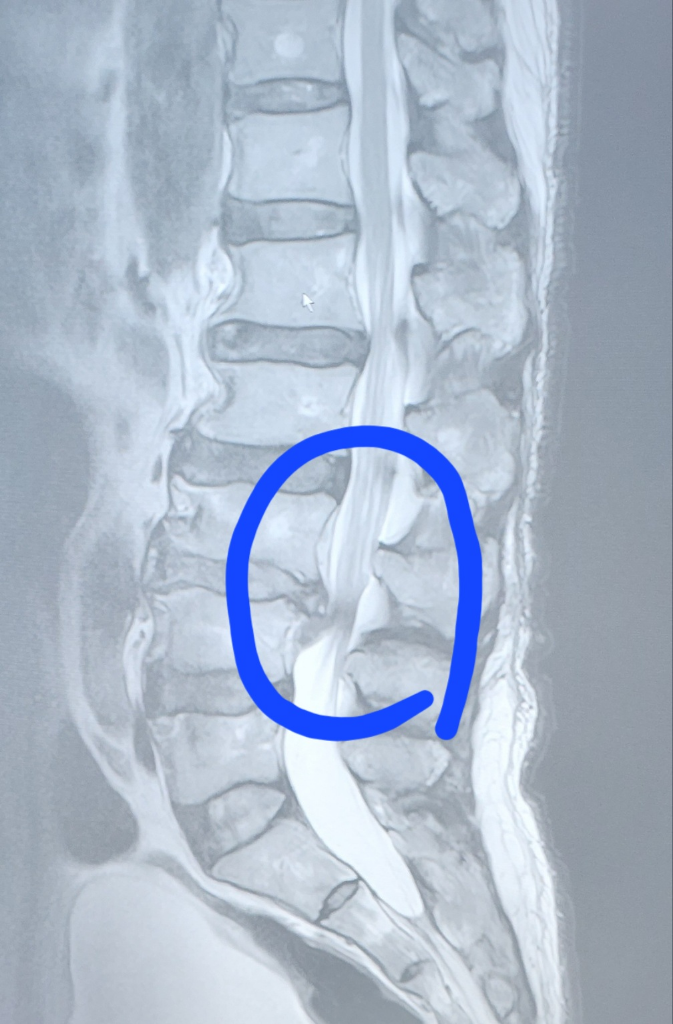

부모님 허리 상태 사진 봐주세요 디스크가 심한 편인가요?

부모님이 병원 다녀오시고 엠알아이 찍은 사진 보내 주셨는데 지금 체크된 부분이 디스크 협착 파열 되신게 맞으신건지요?

디스크 몇번인지 알려주시면 감사하겠습니다

• 1번 째 사진

현재 심한 병변 부위는 요추 3-4번 사이 추간판의 가능성이 있습니다. 사진과 별개로 신경학적 증상이 있다면 필요시 응급 감압술이 필요할 수도 있으므로 진료를 본 담당의사와 상의하는 것이 가장 정확합니다.

현재 MRI단면상으로 정확한 진단은 어려움이 있지만 요추 3-4번의 디스크 탈출증 및 요추 4-5번의 협착증이 관찰됩니다.

우선 마비 증상 등이 없으신 상태라면 신경차단주사 및 약물요법을 시행하시면서 경과관찰을 해보시는 것이 좋겠습니다.